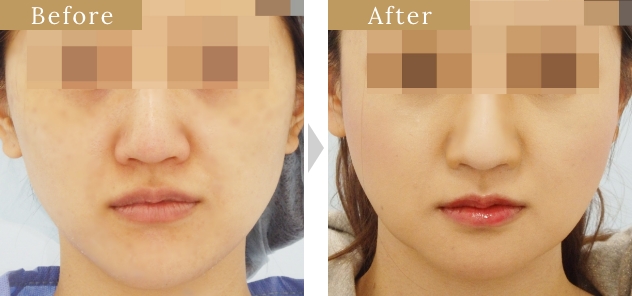

症例

症例